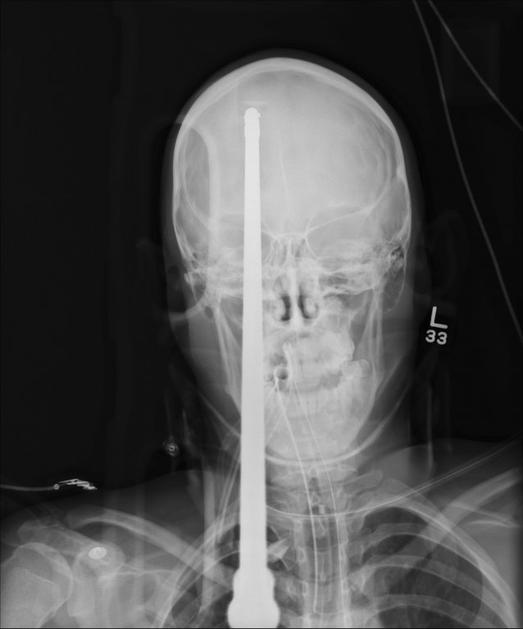

Glavo mu je preluknjala harpuna